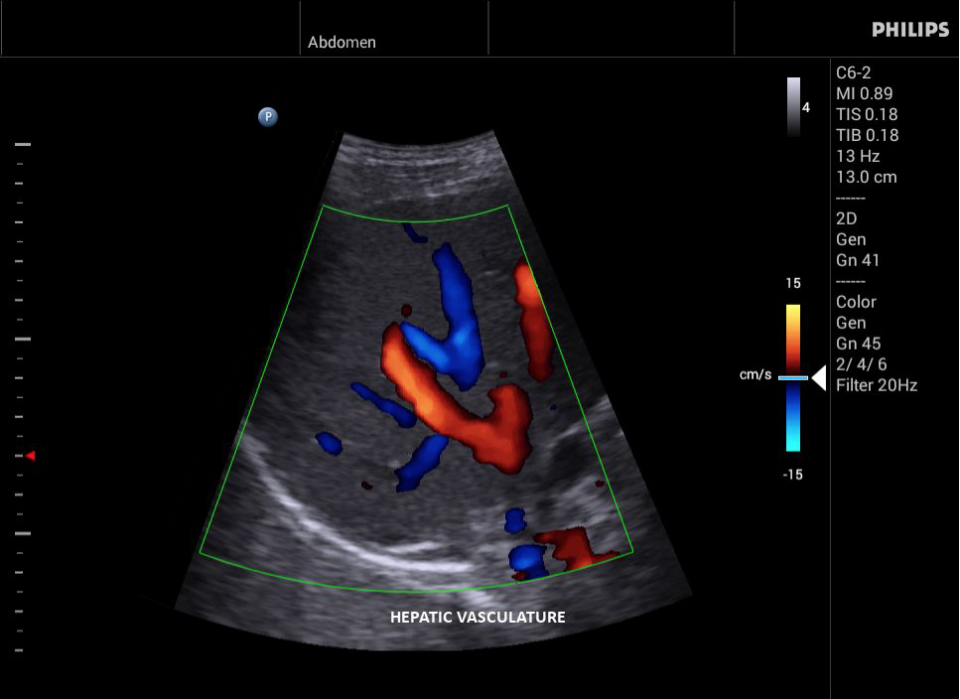

• Исследования сосудов;

• Дуплексный режим: Одновременное отображение режимов 2D и допплера.

• Триплексный режим: Одновременное отображение режимов 2D, допплера и цветного допплера или энергетического допплера.

• Цветное допплеровское картирование